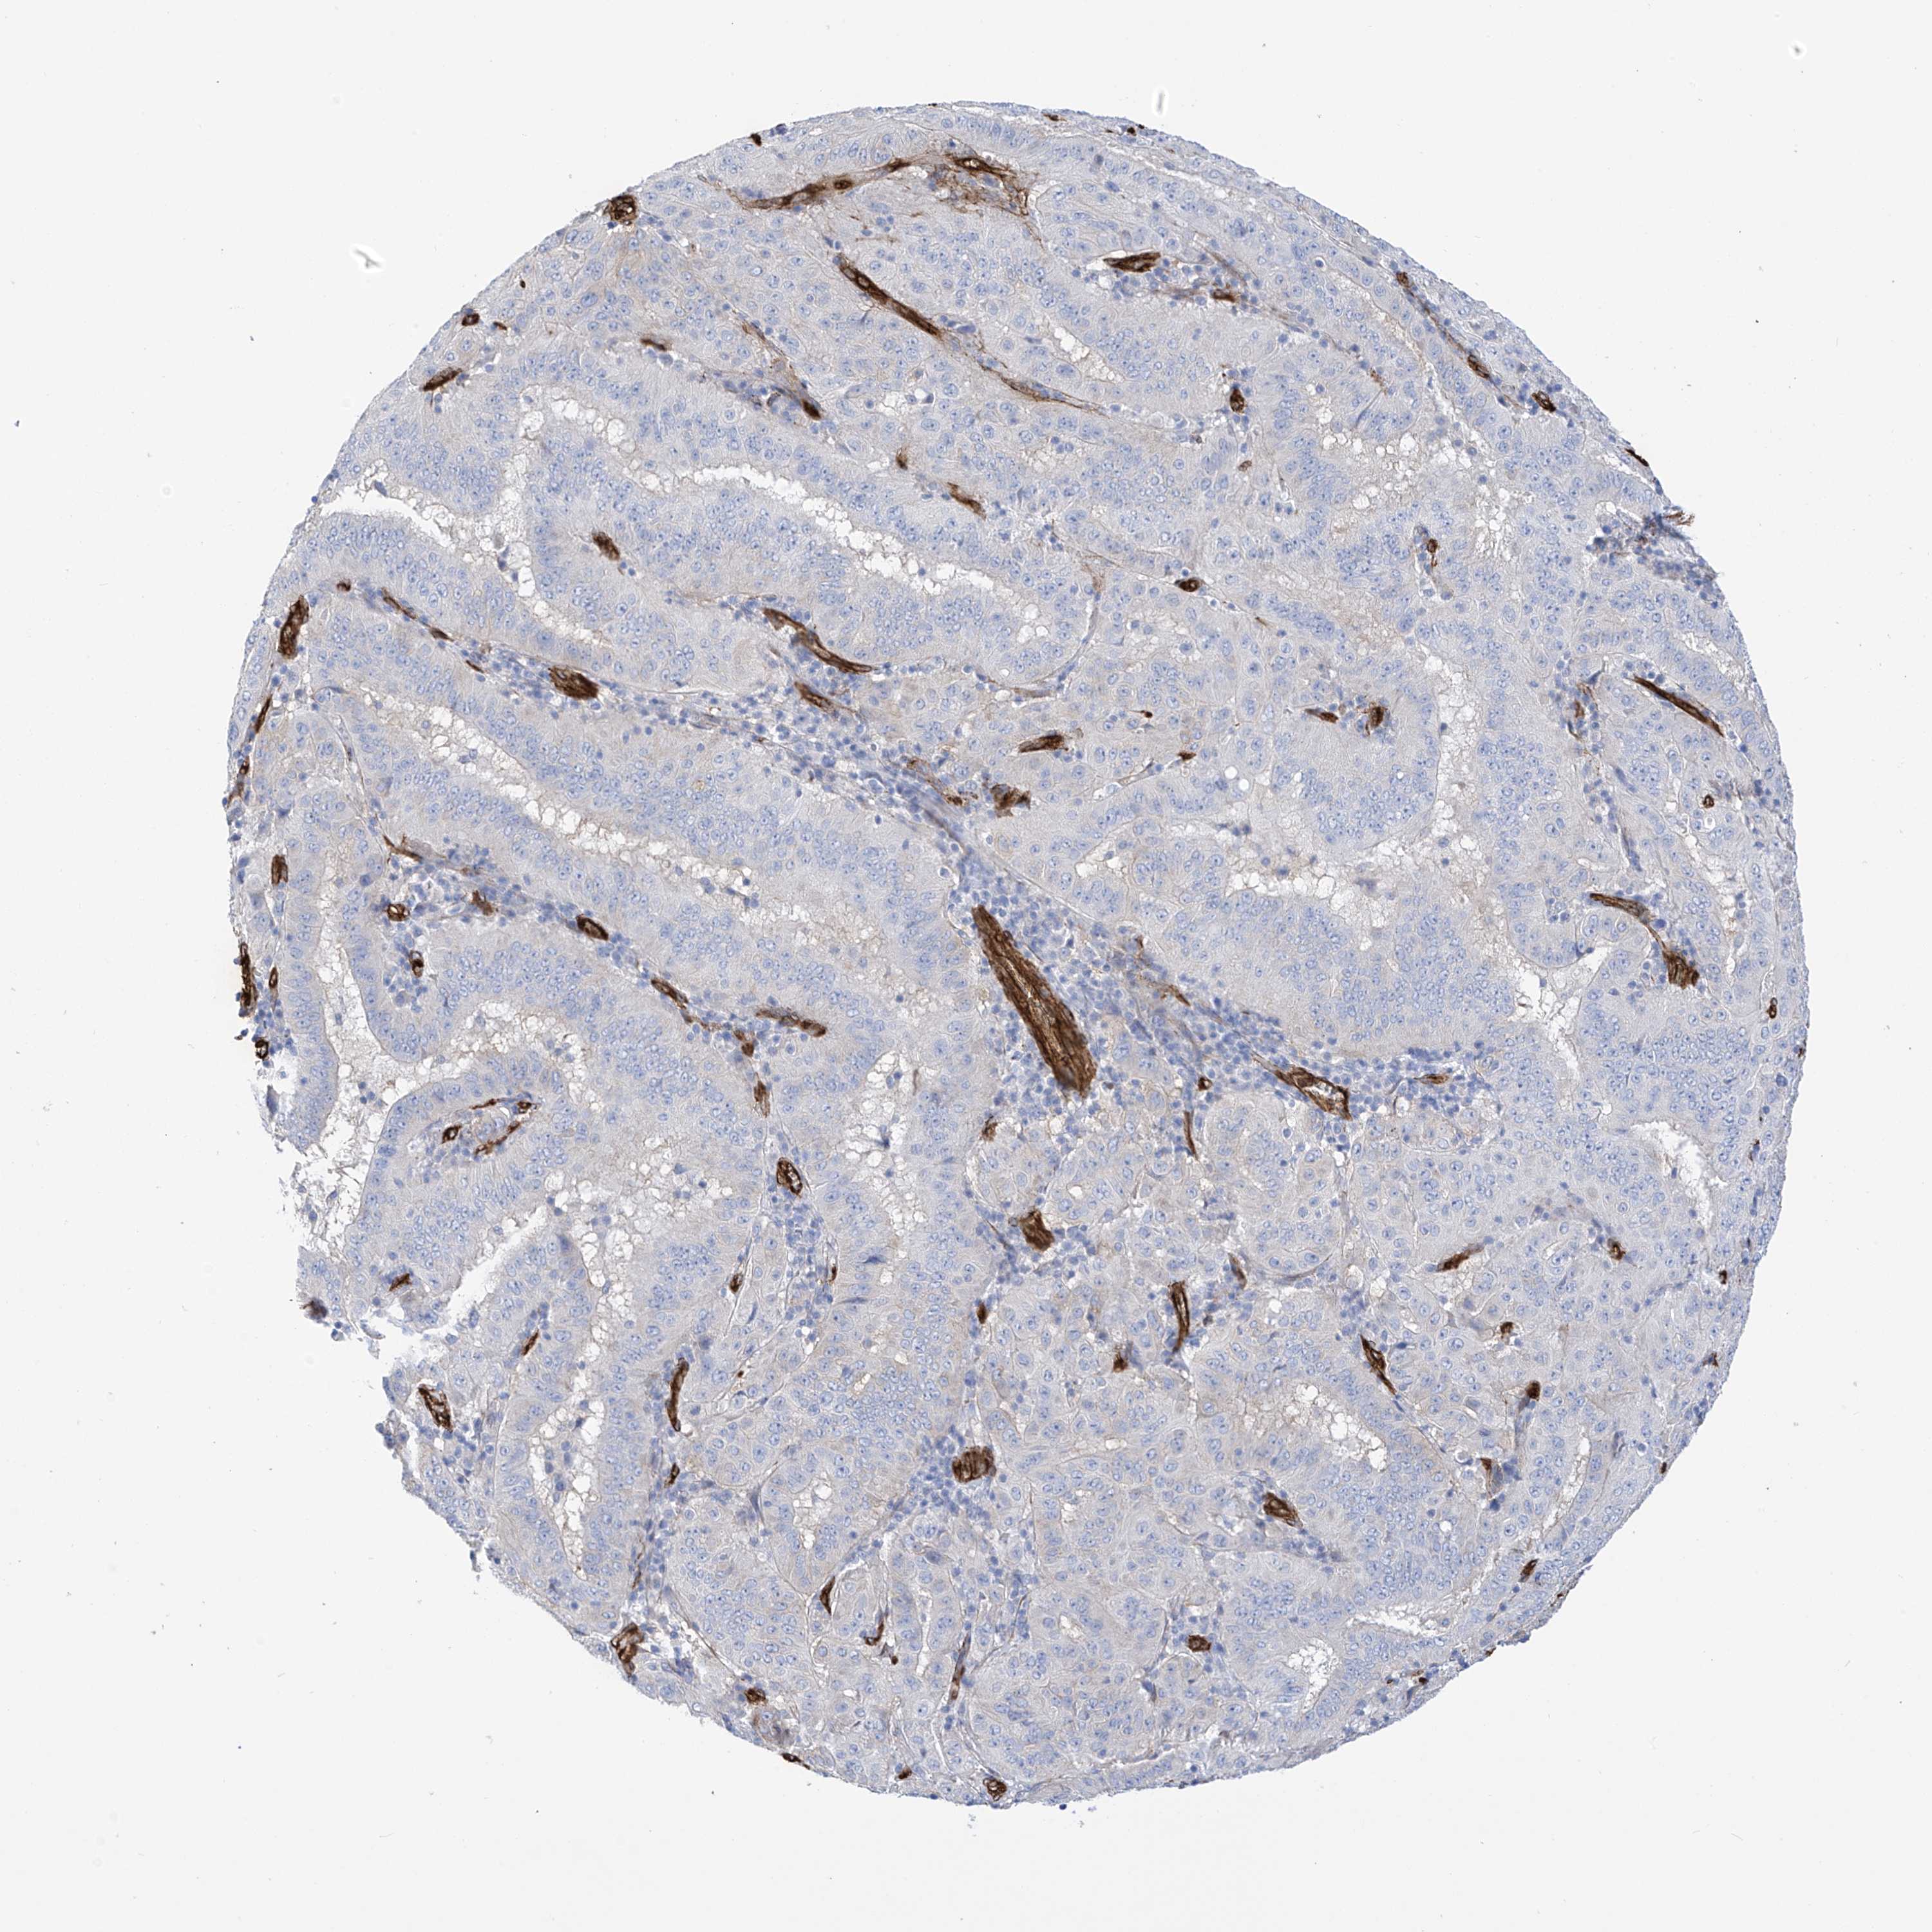

PANCREATIC CANCER - Protein expressioni

A mouse-over function shows sample information and annotation data. Click on an image to view it in a full screen mode. Samples can be filtered based on level of antibody staining by selecting one or several of the following categories: high, medium, low and not detected. The assay and annotation is described here.

Note that samples used for immunohistochemistry by the Human Protein Atlas do not correspond to samples in the TCGA dataset.

Antibody stainingi

Antibody staining in the annotated cell types in the current human tissue is reported as not detected, low, medium, or high, based on conventional immunohistochemistry profiling in selected tissues. This score is based on the combination of the staining intensity and fraction of stained cells.

Each image is clickable and will lead to virtual microscopy that enables deeper exploration of all samples and also displays staining intensity scores, fraction scores and subcellular localization as well as patient and tissue information for each sample.

Antibody HPA034825

Staining

High

Medium

Low

Not detected

Intensity

Strong

Moderate

Weak

Negative

Quantity

>75%

75%-25%

<25%

None

Location

Nuclear

Cytoplasmic/membranous

Cytoplasmic/membranous,nuclear

Adenocarcinoma, NOS